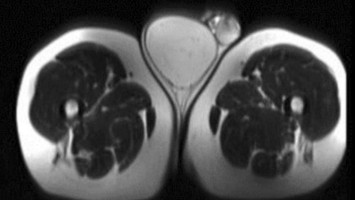

In ihrer neuen S2k-Leitlinie zur systemischen Sklerose hat die Deutsche Gesellschaft für Rheumatologie der Herzbeteiligung ein eigenes Kapitel gewidmet. Troponin als Biomarker spielt darin eine wichtige Rolle, ebenso das Kardio-MRT. Neben der kardiologischen Basistherapie sind Immunsuppressiva unverzichtbar.

Tabletten werden in Hand geschüttet/© O.Farion / Stock.adobe.com (Symbolbild mit Fotomodell), Mann appliziert Salbe auf sein Knie/© Ake Ngiamsanguan / Getty Images / iStock (Symbolbild mit Fotomodell), Cannabisarzneimittel/© [M] Rocky89 / Getty images / iStock, Störung der Lidhebung bei Myasthenia gravis/© Alessandro Grandini / stock.adobe.com (Symbolbild mit Fotomodell), Arzt untersucht Patient mit Rückenschmerzen/© gilaxia / Getty Images / iStock (Symbolbild mit Fotomodellen), Junger bärtiger Mann liegt im Bett und hält sich die Stirn/© kleberpicui - stock.adobe.com (Symbolbild mit Fotomodell), Vordere Kreuzbandruptur/© Springer-Verlag Berlin Heidelberg 2016, Liposarkom des Funiculus spermaticus/© Springer Medizin Verlag GmbH, Behandschuhte Hände drücken Stumpf nach Amputation/© Vitaly Zubrytsky / stock.adobe.com (Symbolbild mit Fotomodellen), Untersuchung des Beins eines Patienten/© Visionär / Fotolia, Mann erhält einen CT-Scan /© Mark Kostich / stock.adobe.com (Symbolbild mit Fotomodell), Arzt untersucht Senior am Rücken/© miodrag ignjatovic / Getty Images / iStock (Symbolbild mit Fotomodellen), Bildgebung verschiedener interstitieller Lungenerkrankungen/© Christoph Lederer et al. / all rights reserved Springer Medizin Verlag GmbH, Kleinkind und Teddy mit Verband/© simoningate / Getty Images / iStock (Symbolbild mit Fotomodell), Frau unkenntlich fasst sich ans Knie/© Pornpak Khunatorn / Getty Images / iStock (Symbolbild mit Fotomodell), Ein älteres Paar läuft mit Stöcken im Wald/© Roman / Stock.adobe.com (Symbolbild mit Fotomodell), Illustration zur künstlichen Intelligenz/© Toowongsa / Stock.adobe.com (Symbolbild mit Fotomodell), Ärztin untersucht Patientin mit Knieschmerz/© Jirapong / Stock.adobe.com (Symbolbild mit Fotomodell), Arzt untersucht älteren Mann/© contrastwerkstatt / Stock.adobe.com (Symbolbild mit Fotomodellen), Blutabnahme/© Yakobchuk Olena / stock.adobe.com (Symbolbild mit Fotomodell), Point-of-care-Ultraschall bei Trauma/© Vicent O et al. / all rights reserved Springer Medizin Verlag GmbH, Röntgenbild Kiefer/© Aniuszka / Fotolia (Symbolbild mit Fotomodell), Box mit Tabletten/© ekachai050050 / stock.adobe.com (Symbolbild), Manuelle Behandlung unterer Rückenschmerzen/© Viorika / Getty Images / iStock (Symbolbild mit Fotomodellen), Operationssaal-Korridor /© h368k742 / stock.adobe.com, Ohnmächtige ältere Frau/© Satjawat / stock.adobe.com (Symbolbild mit Fotomodellen), Akupunktur/© (M) geargodz / stock.adobe.com (Symbolbild mit Fotomodell), Hand greift nach Skalpell/© Morsa Images / Getty Images / iStock, Gruppe beim Rückentraining im Fitnesscenter/© Robert Kneschke / stock.adobe.com (Symbolbild mit Fotomodellen), Mann auf dem Bau/© pololia / Stock.adobe.com (Symbolbild mit Fotomodell), Psychotherapeutische Sitzung/© PeopleImages / Getty Images / iStock (Symbolbild mit Fotomodellen), Frau sitzt besorgt beim Arzt und hält sich den Kopf/© M+Isolation+Photo / Stock.adobe.com (Symbolbild mit Fotomodell), Seniorin liegt reglos auf Boden/© Racle Fotodesign / stock.adobe.com (Symbolbild mit Fotomodell), Medizinisches Personal hält verschiedenfarbige Kinesiotapes/© Татьяна Волкова / stock.adobe.com (Symbolbild mit Fotomodell), Ärztin in Op.-Kleidung/© shapecharge / Getty Images / iStock (Symbolbild mit Fotomodell), Skoliose/© Springer Medizin, Vordere Kreuzbandruptur/© Müller P E & Niethammer T R / all rights reserved Springer Medizin Verlag GmbH, Rettungsdienst/© huettenhoelscher / Getty images / iStock (Symbolbild mit Fotomodellen), Person hält zwei Tabletten in der Hand/© AsiaVision / Getty Images / iStock (Symbolbild mit Fotomodell), Video-Therapie /© Valerii Honcharuk / stock.adobe.com (Symbolbild mit Fotomodellen), Ältere Person hält sich das Knie/© ZayNyi / Stock.adobe.com (Symbolbild mit Fotomodell), Fallbeispiel Röntgenaufnahme des Thorax in zwei Ebenen/© Reinke L. et al. / all rights reserved Springer Medizin Verlag GmbH, Kleiner Junge nach Fahrradunfall/© JohnAlexandr / Getty Images / iStock (Symbolbild mit Fotomodell), Läufer umfasst sein Sprunggelenk/© PeopleImages / Getty Images / iStock (Symbolbild mit Fotomodell), Mann mit Knieschmerzen/© Rockaa / Getty Images / iStock (Symbolbild mit Fotomodell), Vorbereitung eines periphere Venenverweilkatheter/© Seppographie / stock.adobe.com, Springer Medizin Podcast - Stürze im Alter/© Gatz M et al / all rights reserved Springer Medizin Verlag, Orthese und Gehhilfen/© Ralf Geithe / stock.adobe.com (Symbolbild mit Fotomodell), Mann geht mit Hund an der Leine spazieren/© K. Thalhofer / stock.adobe.com (Symbolbild mit Fotomodell), Schenkelhalsfraktur prä- und postoperativ/© Henze K et al. / all rights reserved Springer Medizin Verlag GmbH, Älterer Arzt mit Arzthelfer schauen über Patientenakte/© stokkete / stock.adobe.com (Symbolbild mit Fotomodellen), Röntgenbild Hand/© Mathias Weil / stock.adobe.com, Hinweisschild Notaufnahme/© huettenhoelscher / Getty images / iStock, Frau sitzt vor mehreren Bildschirmen/© Baba Images / stock.adobe.com (Symbolbild mit Fotomodell), Junge Ärztinnen und Ärzte diskutieren/© fizkes / stock.adobe.com (Symbolbild mit Fotomodellen), Systemischer Lupus erythematodes Gesicht Mann/© velimir / Stock.adobe.com (Symbolbild mit Fotomodell), Operation Karpaltunnelsyndrom/© Gardinovacki / Getty Images / iStock (Symbolbild mit Fotomodell), CAR-T-Zellen/© Meletios Verras / Getty Images / iStock, Ärztin untersucht älteren Mann/© Drazen Zigic / Getty Images / iStock (Symbolbild mit Fotomodellen), Frau zieht Patientin Thrombosestrumpf an/© tibanna79 / stock.adobe.com (Symbolbild mit Fotomodellen), Wirbelsäulen-MRT bei Patient mit axialer Spondyloarthritis/© Springer Medizin, Frau bei Knochenmineraldichte-Messung/© gelmold / stock.adobe.com (Symbolbild mit Fotomodell), Psoriasisarthritis /© Springer Medizin, Anatomischer Überblick Handgelenk/© Deglmann CJ / all rights reserved Springer Medizin Verlag GmbH, Frau mit Hut im Wald/© (M) encierro / stock.adobe.com (Symbolbild mit Fotomodell), Rheumatoide Arthritis in den Händen/© RFBSIP / stock.adobe.com (Symbolbild mit Fotomodell), Frau und Mann joggen im Wald/© Harbucks / Getty Images / iStock (Symbolbild mit Fotomodellen), Frau mit Knieschmerzen/© shurkin_son / Getty Images / iStock (Symbolbild mit Fotomodell), Hallux valgus/© masanyanka / stock.adobe.com, Raucher Zigarette Rauch /© buenaventura13 / stock.adobe.com (Symbolbild mit Fotomodell), Magnetresonanztomographie/© Svitlana / Stock.adobe.com (Symbolbild mit Fotomodell), Anästhesistin im OP/© stefanamer / Getty Images / iStock (Symbolbild mit Fotomodellen), Verband an Unterschenkelstumpf wird angelegt/© angkhan / stock.adobe.com (Symbolbild mit Fotomodellen), Schreiendes Baby/© AzmanL / Getty Images / iStock (Symbolbild mit Fotomodell), Narbe nach Kniegelenkersatz/© Miriam Dörr / Fotolia (Symbolbild mit Fotomodell), Mann untersucht Frau an der Lende/© pololia / stock.adobe.com (Symbolbild mit Fotomodell), Gebrochener Arm eines Kindes erhält Gips/© Rafael Ben-Ari / stock.adobe.com (Symbolbild mit Fotomodellen), Unikompartimentelle Knieprothese/© NICOLAS LARENTO / stock.adobe.com, Frankfurt am Main an einem heißen Sommertag mit strahlender Sonne und großem Thermometer/© Günter Albers / Stock.adobe.com, Infantiles Hämangiom/© tolgart / Getty Images / iStock (Symbolbild mit Fotomodell), Zecke auf menschlicher Haut/© sasel77 / stock.adobe.com, Urinbecher und Urinanalyse-Streifen/© RHJ / Stock.adobe.com, Walking mit Kniebandage/© Suzi Media Production / Getty Images / iStock (Symbolbild mit Fotomodell), Fraktur der lateralen Condyle des Humerus im Röntgenbild/© Susmit / stock.adobe.com, Arzt untersucht Knie einer Seniorin/© FluxFactory / Getty Images / iStock (Symbolbild mit Fotomodellen), Röntgenbild einer Psoriasis-Arthritis/© Springer Medizin Verlag GmbH, Frau macht Gymnastikübung in ihrem Schlafzimmer/© Krakenimages.com / stock.adobe.com (Symbolbild mit Fotomodell), Abklärung von Rückenschmerz bei älterer Patientin/© andreswd / Getty Images / iStock (Symbolbild mit Fotomodellen), Physiotherapeut behandelt Patientin an Schulter/© © contrastwerkstatt / stock.adobe.com (Symbolbild mit Fotomodellen), Wald/© alexugalek / stock.adobe.com, Arthropedia, Kinesiotape um das Knie herum/© baranq / stock.adobe.com (Symbolbild mit Fotomodell), Röntgenbild eines künstlichen Hüftgelenks/© Nicolas Larento / Fotolia, Prähabilitation am Fußgelenk/© herraez / Getty Images / iStock (Symbolbild mit Fotomodellen), Junge Ärztin vor einem Triage-Zelt/© Milos / Stock.adobe.com (Symbolbild mit Fotomodell)